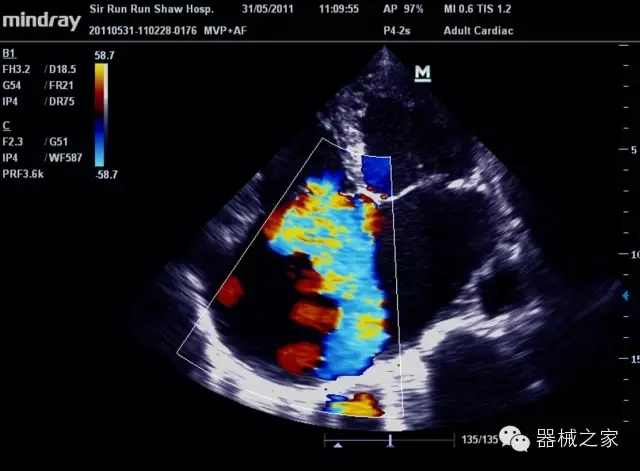

臨床圖片賞析

產(chǎn)品特點(diǎn)

·裝載有采用Multi-Core多核處理的非嵌入式平臺,成像效率大大提高,并且能夠給用戶帶來高速、多任務(wù)并行信號處理體驗(yàn);

·優(yōu)秀的圖像效果、強(qiáng)大的功能體驗(yàn)、豐富的探頭選擇、合理的便攜式設(shè)計(jì),全中文顯示及病人管理界面,使得M7在任何場合、任何時(shí)候都能快速響應(yīng)更好的心血管、腹部、婦產(chǎn)、小器官等常規(guī)超聲檢查以及肌骨、神經(jīng)、顱腦、術(shù)中等新興領(lǐng)域的使用需求;

8倍波束并行處理系統(tǒng)

·在便攜式緊湊平臺上采用更多倍波束并行接收信號處理模式,無論二維還是彩色血流圖像狀態(tài)下,擁有更靈敏的回波頻移捕獲能力,大大提高時(shí)間分辨率,尤其使得心血管表現(xiàn)更為突出;

PSHI?寬帶頻移諧波技術(shù)

·在普通組織諧波的基礎(chǔ)上,通過精確控制的波束形成器,發(fā)射兩組具有相位偏差反向的信號,并采用并行信號處理,數(shù)字化合成并采樣回波信號,在高靈敏度的濾波器的處理過程中獲取更純凈的諧波信號,使圖像具有更加出眾的細(xì)節(jié)分辨率;

iClear®+iBeam?

·智能化按線復(fù)合多角度獲取聲束的原始信號,配合智能化的斑點(diǎn)噪聲識別及控制處理技術(shù),整體提高組織結(jié)構(gòu)細(xì)節(jié)分辨率,任何時(shí)候都能快速響應(yīng),更好的滿足心血管的使用需求;

支持全新3T工藝探頭群

·包括探頭材料、結(jié)構(gòu)設(shè)計(jì)、加工工藝三方面的革新技術(shù)給圖像帶來品質(zhì)的飛躍;